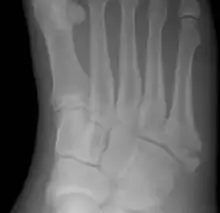

A Jones fracture is a broken bone in a specific part of the fifth metatarsal of the foot between the base and middle part[8] that is known for its high rate of delayed healing or nonunion.[4] It results in pain near the midportion of the foot on the outside.[2] There may also be bruising and difficulty walking.[3] Onset is generally sudden.[4]

The fracture typically occurs when the toes are pointed and the foot bends inwards.[6][2] This movement may occur when changing direction while the heel is off the ground such in dancing, tennis, or basketball.[9][10] Diagnosis is generally suspected based on symptoms and confirmed with X-rays.[3]

Initial treatment is typically in a cast, without any walking on it, for at least six weeks.[5] If, after this period of time, healing has not occurred, a further six weeks of casting may be recommended.[5] Due to poor blood supply in this area, the break sometimes does not heal and surgery is required.[3] In athletes, or if the pieces of bone are separated, surgery may be considered sooner.[5][8] The fracture was first described in 1902 by orthopedic surgeon Robert Jones, who sustained the injury while dancing.[11][4]